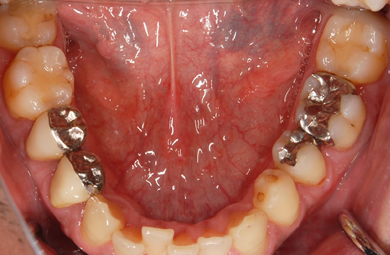

| 性別/年齢 | 男性 / 33歳 | ||||||||||||||||||||||||||||||||

| 主訴 | 痛みがある。 | ||||||||||||||||||||||||||||||||

| 治療方針 | 透明感のあるオールセラミックを使用して審美的・機能的回復を行う。 | ||||||||||||||||||||||||||||||||

| 治療内容 | オールセラミック6本(オールセラミック用の土台2本) | ||||||||||||||||||||||||||||||||